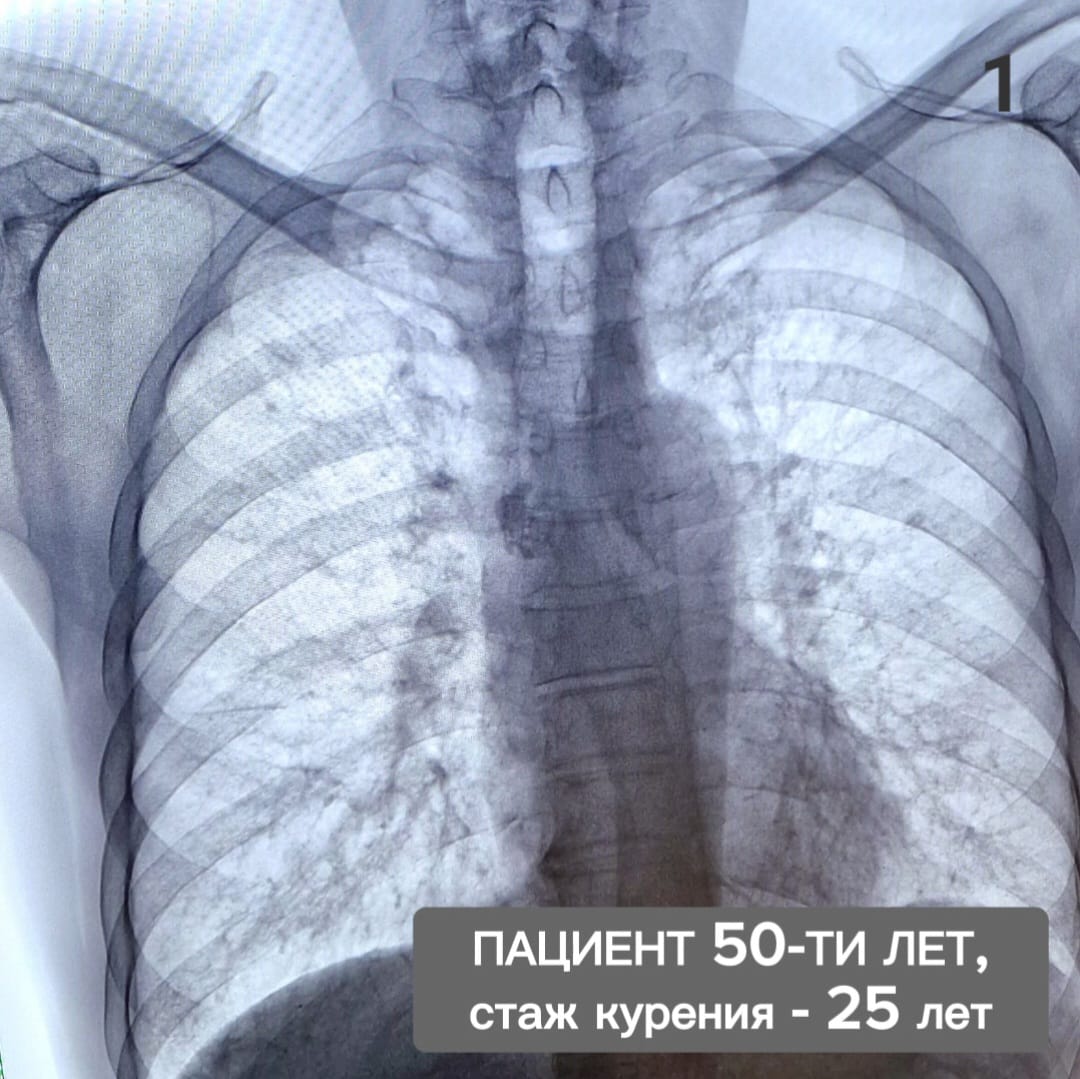

Влияние вейпа на легкие: Фотографии и исследования

Раздел: Визуальный дайджест